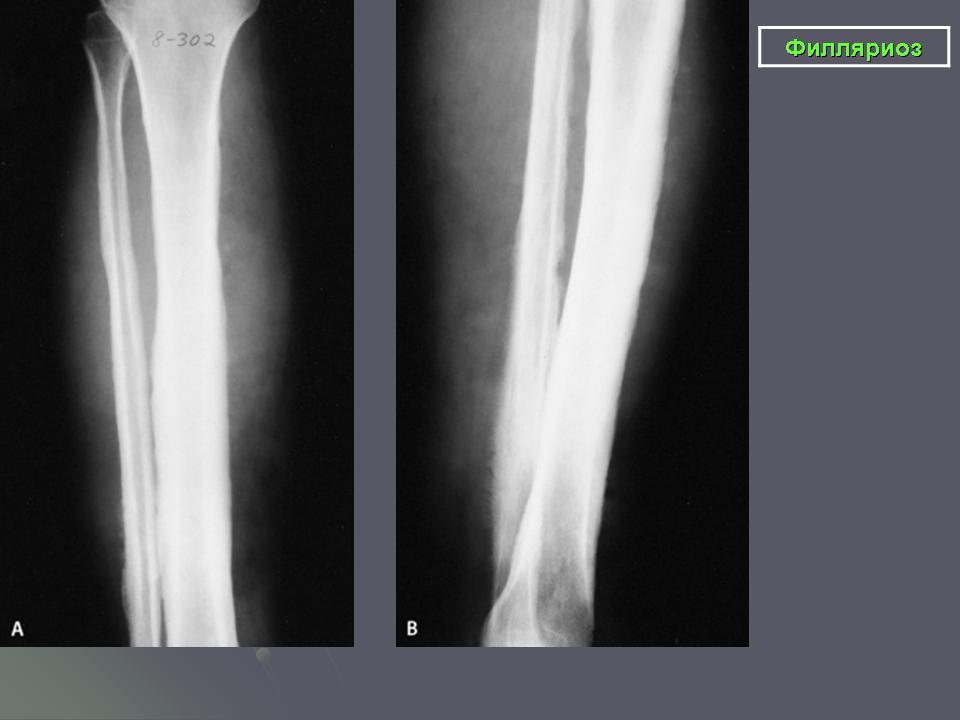

Вухерериоз распространен более широко (тропики и субтропики). Введенные комарами личинки червя поселяются в лимфатических узлах (чаще в паховых), вызывая лихорадку, воспаление лимфатических сосудов, а спустя годы утолщение (слоновость) нижних конечностей, мошонки, грудных желез и т. д.